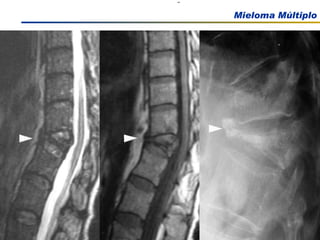

Comprometimento Ósseo

Dor ossea Presente em 2/3 dos pacientes com mieloma: dorso e tórax Agravada pelo movimento. Dor persistente pode indicar fraturas nas vértebras Manifestações clínicas Medeiros, C. R in Zago, M.A et al, Hematologia; fundamentos e prática, 2001 Hoffman Hematology 5th Edition, 2008

Dor ossea Presenteem 2/3 dos pacientes com mieloma: dorso e tórax Agravada pelo movimento. Dor persistente pode indicar fraturas nas vértebras Manifestações clínicas Medeiros, C. R in Zago, M.A et al, Hematologia; fundamentos e prática, 2001 Hoffman Hematology 5th Edition, 2008

EXAMES COMPLEMENTARES Rx de esqueleto Em casos selecionados: TAC, RNM NCCN Practice guidelines in Oncology – v 2.2009